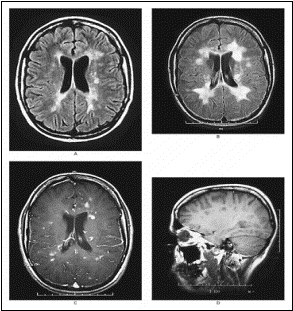

traitement est symptomatique par le méthylprednisolone. A l’IRM de 93, il y

a des anomalies du tronc cérébral en T2, et des prises de contraste

multiples au Gd+ au niveau encéphalique (corticale et corps calleux).

De 93 à 2001, l’IRM montre de nouvelles lésions

multiples importantes et l’aggravation de l’atrophie en particulier au

niveau du corps calleux (facilement mesurable à cet endroit, et constituant

un bon marqueur de l’atrophie cérébrale).